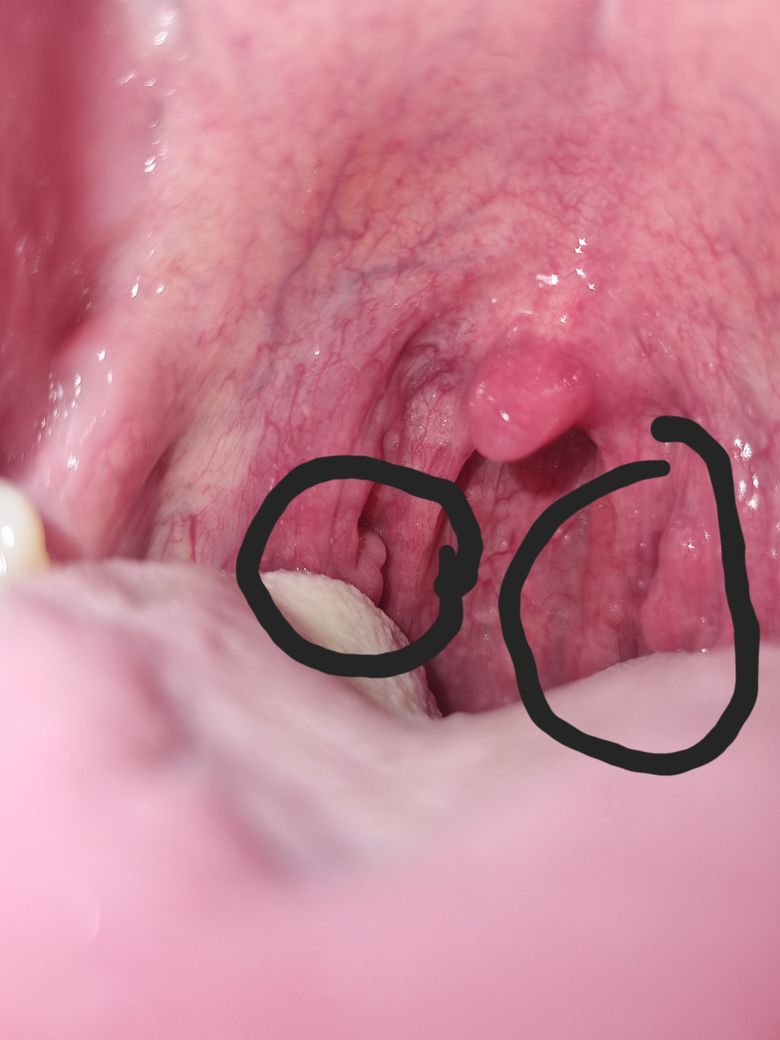

목 편도에 저런게있는대 뭘까요? 큰이상이 아닌가 걱정이 됩니다

오늘 목이 특히 아프고 칼칼해서 들여다봤는대 저런모양이여서 올려봅니다..

현재 사진상만으로 보이는 소견으로만은 정확한 판단은 어렵습니다. 하지만 편도 부위가 발적된 것 외에 특이점을 찾기는 어려운 것 같습니다. 이비인후과에 내원하시어 정확히 진단을 받아보시기 바랍니다.

목에 정상적으로 관찰되고 있는 편도선으로 보이며 편도염증을 자주 경험한 경우

만성 편도선염으로 인해 편도 모양의 변화가 오는 경우도 있습니다. 약간의 편도 비대를

동반하는 것으로 보이며 알레르기 비염이나 역류성 식도염으로 인해 위산이 역류하는

경우에도 편도가 붓는 경우도 있으나 치료가 필요한 편도 비대로 보이지는 않습니다.

편도에 정상적으로 존재하는 주름입니다. 전반적으로 편도의 발적이 있으므로 통증이 있는 경우 진통제를 처방받아 복용해보시기 바랍니다.

정상적인 편도선입니다. 감염이 있으면 편도선염이 걸렸다고 표현하는데 이때 이 편도 부위가 많이 붓게 됩니다.

지금은 붓지 않고 정상적인 모습을 보이고 있습니다.